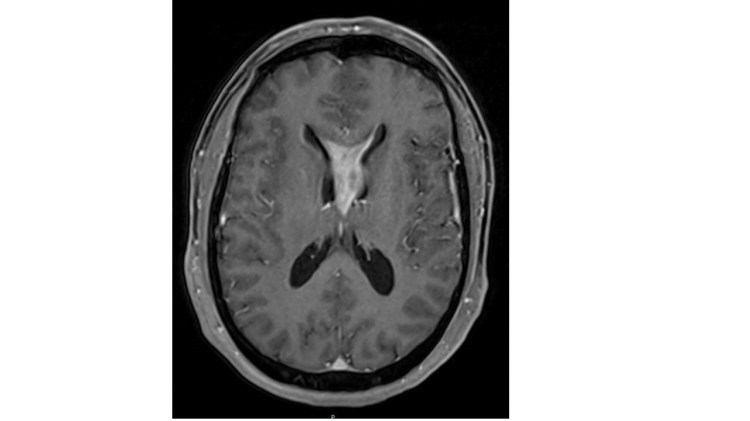

-Metástasis cerebrales: El aumento de los tratamientos para los tumores ha generado un incremento en la tasa de curación y supervencia de los mismos. La aparición de metástasis cerebrales tene lugar sobre todo en pacientes con cáncer de mama y pulmón. Es fundamental llevar a cabo un tratamiento adecuado en cada caso. Gran parte de estos pacientes puede beneficiarse de la cirugía sobre todo aquellos pacientes con metástasis cerebral única en ausencia de afectación tumoral de otros órganos. Tras la intervención se debe administrar tratamiento con radioterapia.